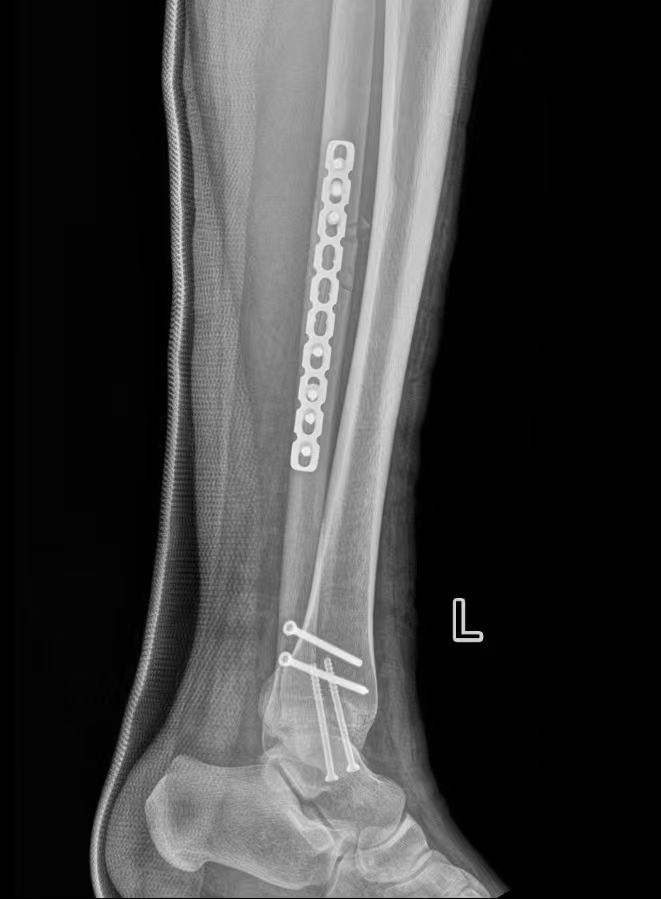

为保障诊疗安全,周占锋团队联合麻醉与围术期医学科、康复医学科开展术前综合评估,结合患者伤情与个体情况制定手术方案,并与患者充分沟通病情、治疗计划及注意事项,缓解其紧张情绪。

术中严格遵循骨科诊疗规范,完成骨折复位与固定,手术过程顺利。